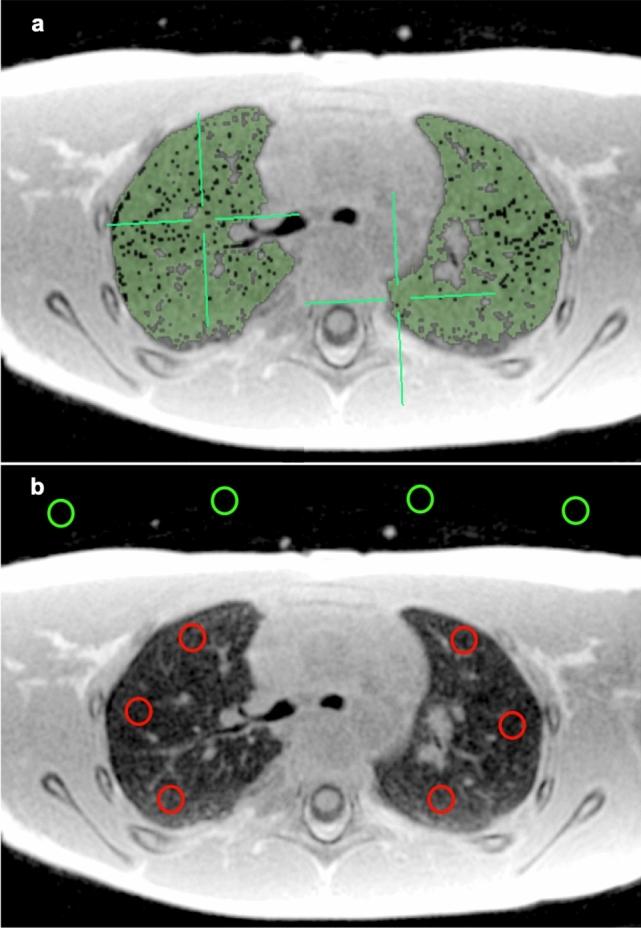

Lung MRI was performed in 17 children with morphologically normal lungs (median age: 4.7 years, range 15 days to 17 years). Both lungs were manually segmented in UTE and ZTE images and the average signal intensities were extracted. Lung-to-background signal ratios (LBR) were compared for both sequences and between both patient groups using non-parametric tests and correlation analysis. Anatomical region-of-interest (ROI) analysis was performed for the normal cohort for assessment of the anteroposterior lung gradient.

There was no significant difference between LBR of normal lungs using UTE and ZTE (p < 0.05). Both sequences revealed a LBR age-dependency with a high negative correlation for UTE (R =  - 0.77; range 2.98-1.41) and ZTE (R =  - 0.82; range 2.66-1.38)). Signal-to-noise (SNR) and contrast-to-noise ratios (CNR) were age-dependent for both sequences. SNR was higher for children up to 2 years old with 3D UTE Cones while for the rest it was higher with 4D ZTE. CNR was similar for both sequences. Posterior lung areas exhibited higher signal intensity compared to anterior ones (UTE 9.4% and ZTE 12% higher), both with high correlation coefficients (R = 0.94, R = 0.97).